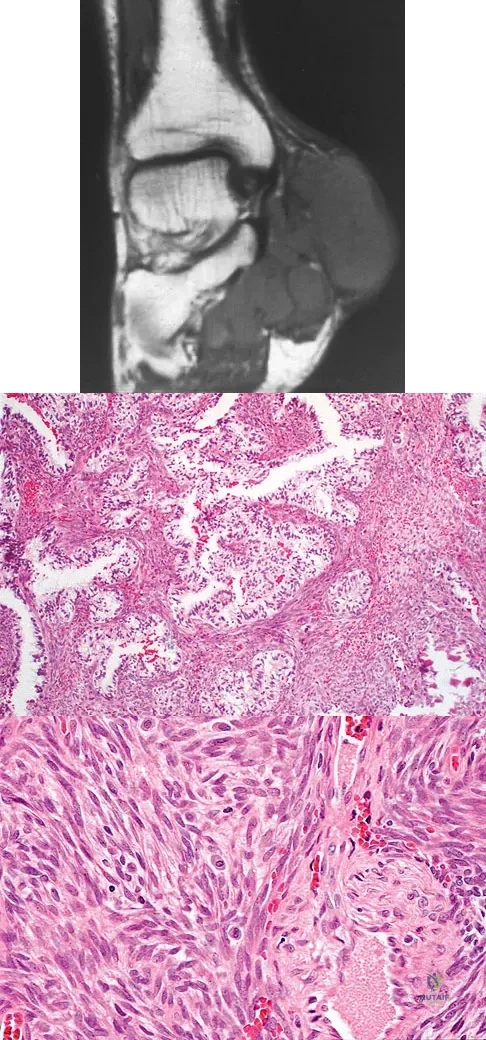

Question 43

A 40-year-old man has a painless mass around his left ankle. He notes minimal growth over the past year. An MRI scan is shown in Figure 73a, and biopsy specimens are shown in Figures 73b and 73c. What is the most likely diagnosis?

Explanation